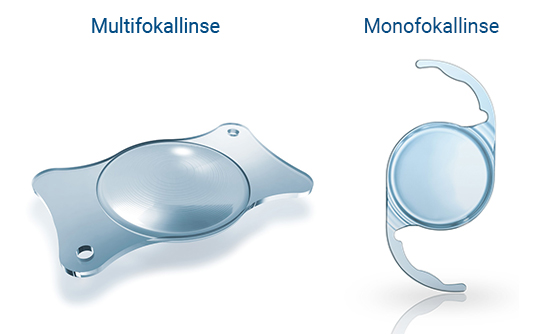

Die Operation erfolgt dabei durch einen ambulant durchgeführten chirurgischen Austausch der getrübten natürlichen Linse mit einer hochmodernen Kunstlinse (Intraokularlinse) – in der Regel mit einer Multifokallinse oder alternativ einer monofokalen Linse. Unsere Augenärzte in den EuroEyes-Kliniken haben bereits mehrere Tausend Graue-Star-Operationen erfolgreich vorgenommen. Die revolutionäre LenSx®-Lasertechnologie ermöglicht sogar eine klingenfreie Implantation.

Der Operateur setzt die neue Linse mit einem Injektor in das Auge ein. Die Linse entfaltet sich und wird vom Operateur in der leeren Linsenhülle richtig platziert. Sie kann ein Leben lang im Auge bleiben und kann entweder monofokal oder multifokal sein. Da eine Monofokallinse nur einen Brennpunkt hat, ist der Patient nach der Operation noch auf eine Brille angewiesen. Eine Multifokallinse hingegen hat mehrere Brennpunkte. Sie ermöglicht scharfes Sehen in unterschiedlichen Entfernungen und so ein brillenfreies Leben.

Die Behandlung des Grauen Star kann mit Mono- oder Multifokallinsen erfolgen. Multifokallinsen haben mehrere Brennpunkte. Der entscheidende Vorteil ist, dass der Patient nach der Behandlung wieder sowohl in der Nähe und mittleren Distanz also auch in der Ferne scharf sehen kann und nicht mehr auf Lese- oder Gleitsichtbrille angewiesen ist. Monofokallinsen weisen im Gegensatz dazu nur einen Brennpunkt auf. Sie können daher nur das Sehen entweder in der Nahe oder in der Ferne verbessern. Die völlige Unabhängigkeit von der Brille kann mit Monofokallinsen nicht gewährleistet werden.

Die Behandlung des Grauen Star kann mit Mono- oder Multifokallinsen erfolgen. Multifokallinsen haben mehrere Brennpunkte. Der entscheidende Vorteil ist, dass der Patient nach der Behandlung wieder sowohl in der Nähe und mittleren Distanz also auch in der Ferne scharf sehen kann und nicht mehr auf Lese- oder Gleitsichtbrille angewiesen ist. Monofokallinsen weisen im Gegensatz dazu nur einen Brennpunkt auf. Sie können daher nur das Sehen entweder in der Nahe oder in der Ferne verbessern. Die völlige Unabhängigkeit von der Brille kann mit Monofokallinsen nicht gewährleistet werden.